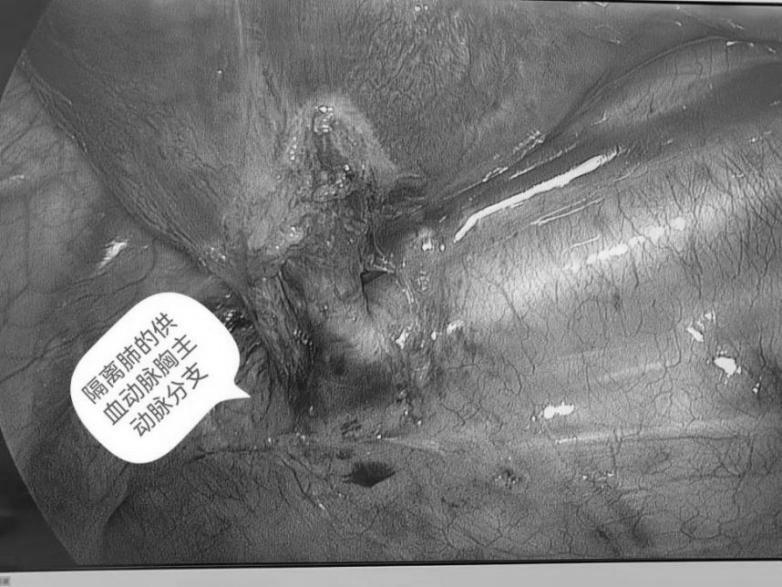

麻醉科朱敦教授等以高超的技术保障了术中多多生命体征的平稳。同时,术中还邀请胸外科张云峰主任医师、高山医师等协助。在手术室、麻醉科、胸外科的通力配合下,曹振杰主任团队在单孔胸腔镜下轻柔地松解病肺周围的粘连,抽丝剥茧,暴露病灶,仔细游离其滋养血管及肺段,当病变肺叶被完整离断取出后大家松了一口气。